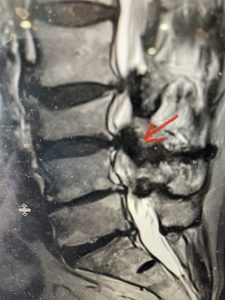

This 66 year-old male with Factor XI deficiency had originally had a decompressive laminectomy L2-S1 and in situ fusion about three years prior for severe thecal sac compression mainly due to severe epidural lipomatosis (Fig 4).

(Fig 4a) Sagittal (a) and Axial (b) T2-weighted lumbar MRI demonstrating severe spinal stenosis L2-5 (arrow)and extruded disc at L3-4 on axial image (arrow)

(Fig 4b)

Epidural lipomatosis is a relatively rare condition where normally present fat in the epidural space is hypertrophied and can cause severe thecal sac compression. It is generally deposited more in the lateral and dorsal epidural space. This can be caused by long term steroid use and obesity, but also can be idiopathic. He had done well until more recently had developed low back pain with bilateral thigh pain and numbness. He had difficulty walking because of the pain. A new MRI (Fig 5) revealed that he had developed severe degeneration of the L1-2 segment above his prior decompression and fusion with a large extruded disc/osteophyte, right greater than left with severe thecal sac compression. He also had some residual T12-L3 residual epidural lipomatosis.

He had failed conservative treatment consisting of neurontin, physical therapy and epidural injections. He underwent revision laminectomy T12-L3 to decompress and explore prior fusion. He did have significant epidural fat encountered particularly at L1-2. The fat in epidural lipomatosis has a much more firm, globular texture. It takes a while to search within the fat, gently dissecting with a Penfield 4, to finally find the thecal sac! We encountered a large subligamentous extruded fragment lateral to the thecal sac on the right above the take off of the L2 nerve root. We removed any more residual fat at the L2-3 level and T12-L1 and decompressed the sac well. On exploration of the prior fusion it was fairly solid, but had some gaps at L2-3 fusion mass. Therefore we added a T12-L3 in situ fusion to augment those gaps and because we were at the thoracolumbar junction we extended fusion to T12. Post operatively he had relief of his leg pain.